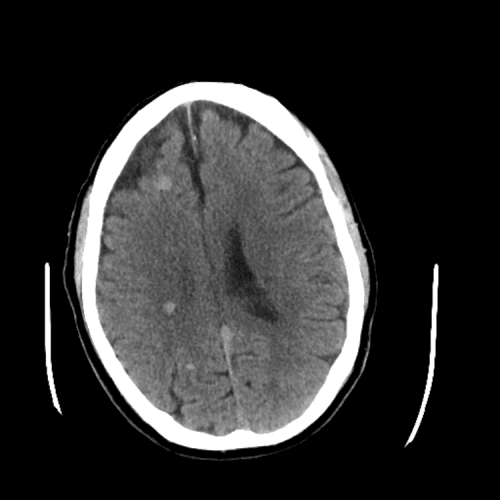

ACA and MCA territory infarct

Case #1